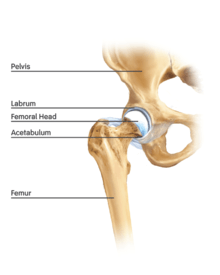

The hip is essentially a ball and socket joint. It consists of the head of the femur (the ball) and the acetabulum (the socket). Both the ball and socket are congruous and covered with hyaline (or articular) cartilage, which allows smooth, almost frictionless gliding between the two surfaces. The edge of the acetabulum is surrounded by the acetabular labrum, a fibrous structure that envelops the femoral head. (See fig. 1) The labrum acts as a seal, or gasket, around the femoral head. However, this is not its only function, as it has been shown to contain nerve endings, which may cause pain if damaged.[18] The blood supply of the labrum has also been demonstrated.[25] The joint itself is encompassed by a thick, fibrous joint capsule, which is lined by synovium. The ligaments that keep the hip joint in place are in fact, thickened areas of joint capsule, rather than distinct structures. The synovium generates fluid that lubricates the joint; in that fluid are the nutrients needed to keep the cartilage cells alive. A total of 27 muscles cross the hip joint, making it a very deep part of the body for arthroscopic access. This is one reason why hip arthroscopy can be quite technically demanding.